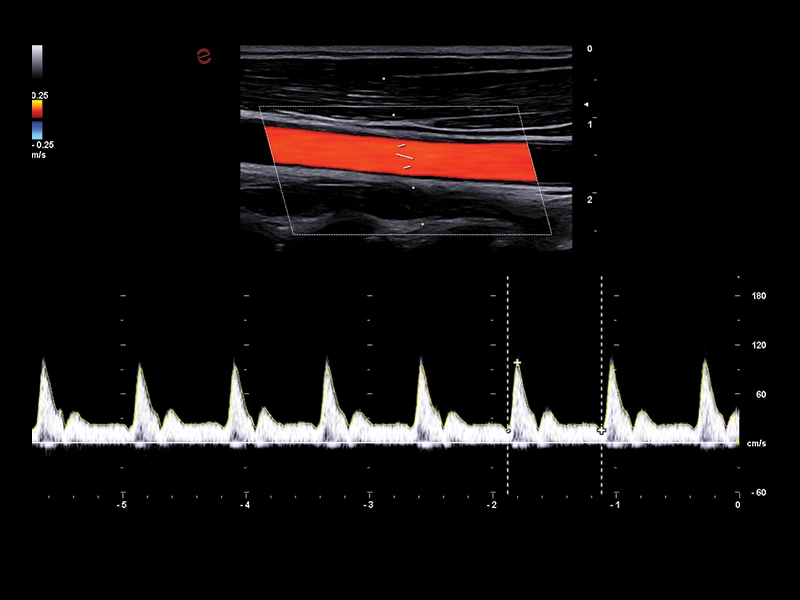

MyLab™Sigma - Mid cerebral artery investigation with PW Doppler mode

MyLab™Sigma - Mid cerebral artery investigation with PW Doppler mode